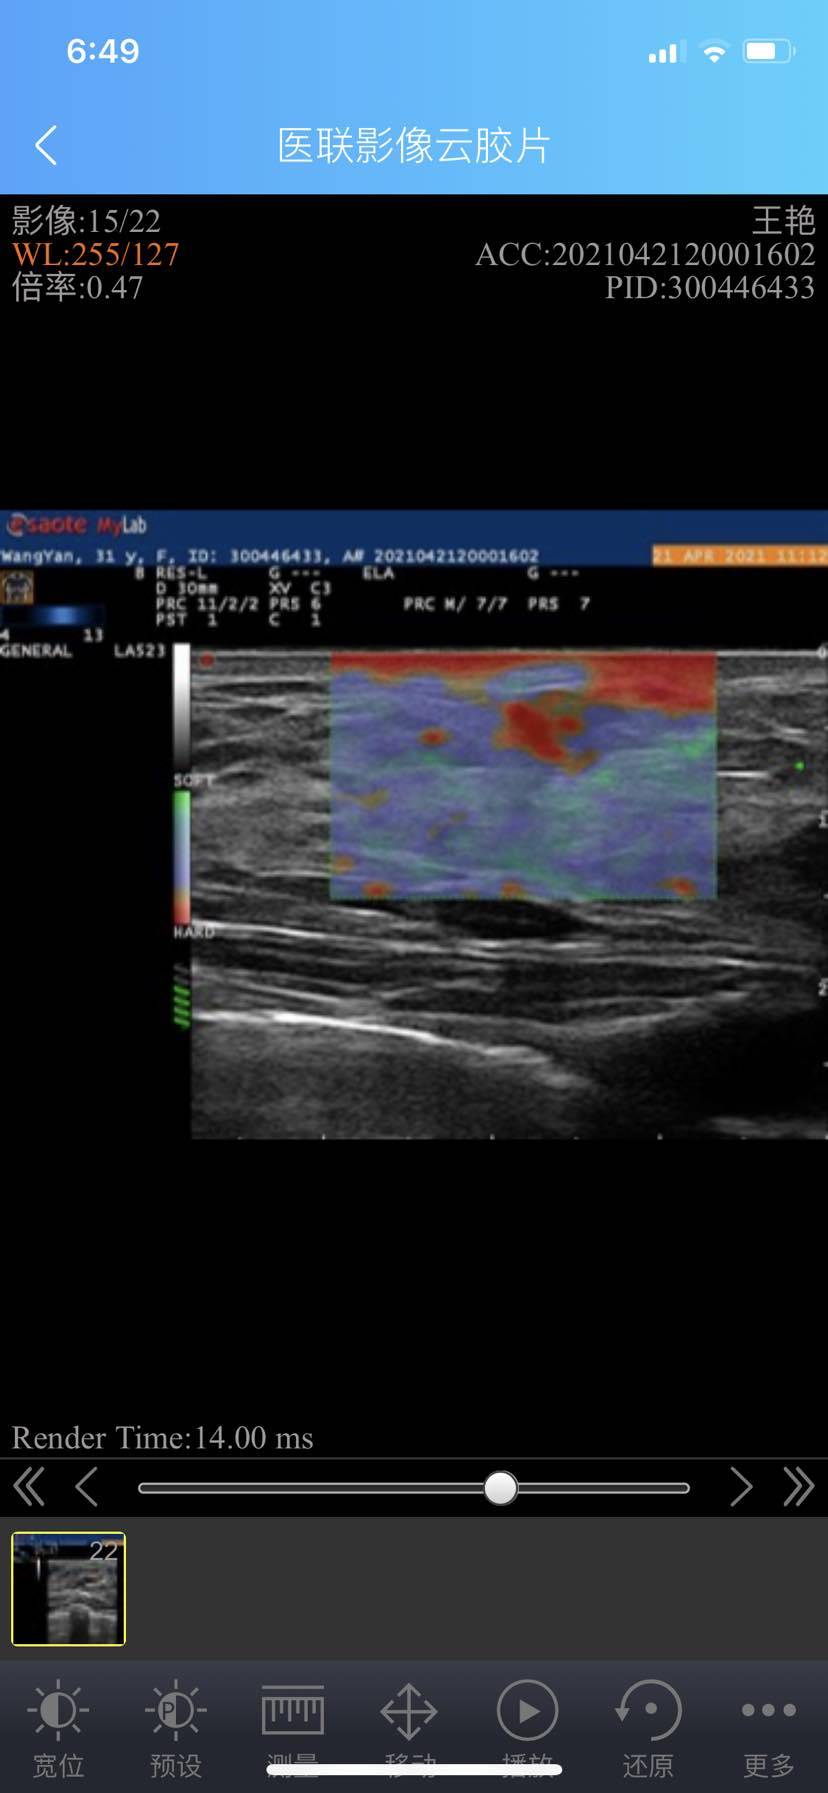

求助 结节不规则 很硬 活动性差 但是在瑞金和华山做b超判定三类

有没有人可以帮忙看看 我的结节很不规则形状 很硬